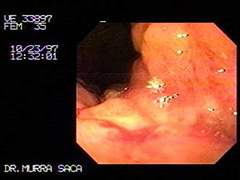

Paciente femenina de 35 años:

Consulta por dolor abdominal de dos meses de evolución, pérdida de peso e ictericia, vómitos de contenido alimenticio con fetidez. Dicha paciente había emigrado hacia los Estados Unidos de Norte América, en sus principios fue diagnosticada como Hepatitis viral A, manejada ambulatoriamente. Pero su cuadro empeoraba por lo que decidió regresar a su país de origen El Salvador.

Fotografía del caso anterior:

Carcinoma Gástrico que ha infiltrado toda la cámara gástrica, se observa el cardias por retroflexión el cual es infiltrado por dicho carcinoma parte negra es el Endoscopio.